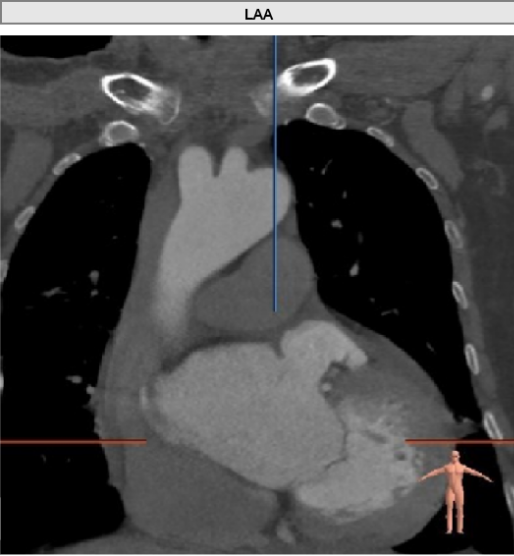

患者为79岁老年男性,因“劳力后胸闷气短5年,加重1周”入院。此次来海军军医大学第二附属医院心内科就诊,心脏超声提示:主动脉重度狭窄伴中度关闭不全;全心增大,左室肥厚;升主动脉瘤样扩张;LVEF:53%。遂以“主动脉狭窄(重度)”收治入院。

左室腔内径尚可,心室壁稍增厚。